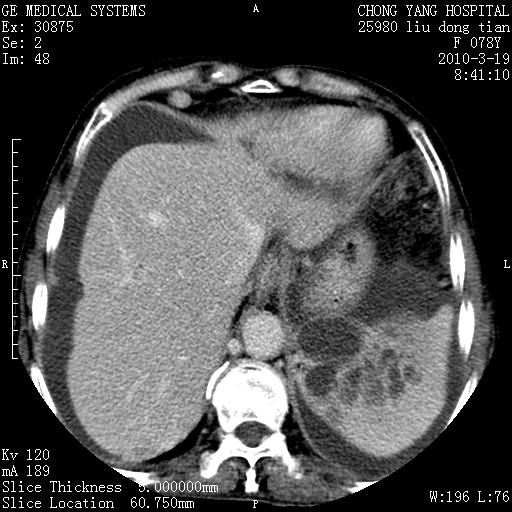

标题: CT25199:F 78Y 腹胀半年 消瘦乏力 [打印本页]

胆囊壁增厚并明显强化,胆囊癌伴多发转移瘤可能性大,淋巴瘤不除外,右肾囊肿,胸腹水.

考虑nhl,肝、脾、腹膜腔及腹膜后多发淋巴结受侵,腹水,右肾囊肿,慢性胆囊炎,右侧少量胸腔积液。

胆囊有软组织影有强化,支持胆囊癌,肝脾、腹膜后淋巴结转移。

nhl的淋巴结多围绕主动脉,而且主动脉会移位,所以不考虑nhl。

分开来讲:肝左叶、尾叶病灶有不均强化像肝癌;

脾脏病灶无强化,像多发囊肿或淋巴管瘤,不除外淋巴瘤(低强化);

胆囊增生性病变:胆囊癌,腺肌增生症,慢性胆囊炎;

肝门、胰腺头、腹膜后多个团块: 淋巴瘤,转移;

腔静脉肝内段细小有无布加可能?

一元论最好了 淋巴瘤所致改变; 胆囊癌转移不像,胆囊周围肝组织清晰,肝癌淋巴结转移?三元论都不止。

最后报的胰头癌多发转移,脾脏单独考虑囊肿或淋巴管瘤。